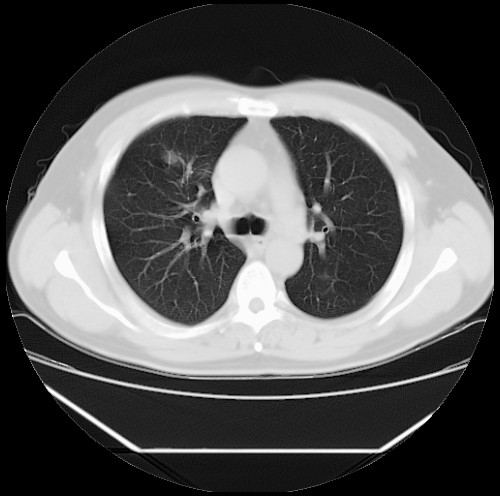

标题: CT22085:双肺多发结节

男,44岁,咳嗽,痰中带血2天。

病灶大部分位于胸膜下,结节大小相差不是很大,肺尖太干净。这种结核没见过,我认为可排除。

除肺内及胸膜下可见多发大结节外,在肺小叶中心核、小叶间隔及支气管血管束上亦可见多方小结节,可以认为是随机分布。考虑转移可能性大。

仔细观察病灶形态,病灶边界部分清楚,结合临床症状,首先考虑转移,纵隔内多个肿大淋巴结影。

双肺血管纹理末端多发类圆形结节,边界光滑清晰 气管前腔静脉后淋巴结肿大

考虑转移瘤

沿血管分布,位于血管末端。转移瘤多见,血行性菌栓也可见到。

本例双肺多发类圆形高密度灶,边清,结合病史多考虑双肺多发转移改变,可以结合实验室检查。